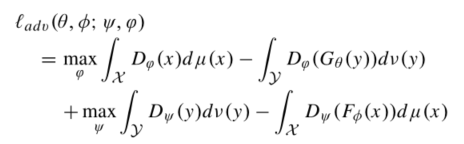

原始的损失函数:

其中: